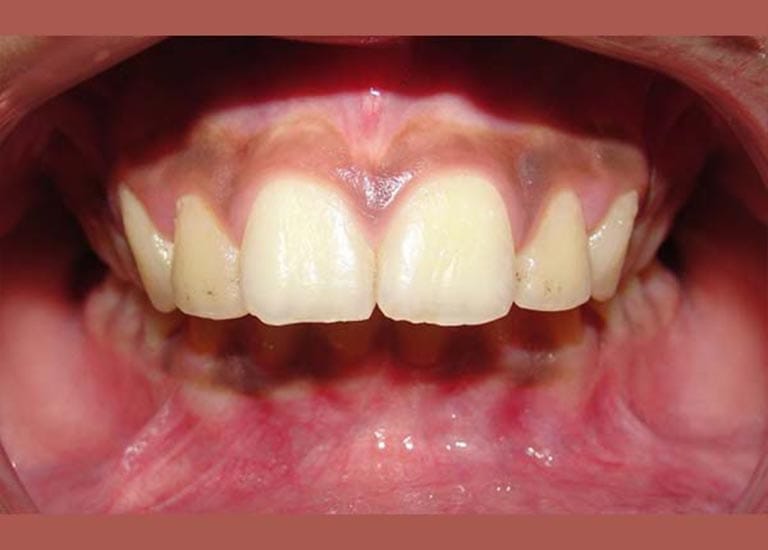

عانى هذا الشاب اليافع من بروز شديد في الأسنان وصل إلى 1 سم، وكان سببه الرئيسي هو تراجع الفك السفلي، وهو ما كان يظهر بوضوح على بروفيل وجهه الجانبي.

كما تظهر الصور، كان التحسن جذرياً ليس فقط في الابتسامة ولكن في تناسق ملامح الوجه بالكامل. تم تصحيح البروز، وتحسنت علاقة الفكين، وحصل الشاب على ابتسامة جميلة وواثقة.